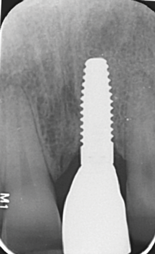

Fig 13. Radiograph after loading, showing solid bone remodeling within the machined implant neck area.

Figure 13

Fig 15. Radiograph at 3-year follow-up, showing stable bone situation compared to control radiograph after loading (Fig 13); note no bone loss.

Figure 15